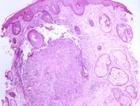

5. 尋常狼瘡:占皮膚結核的10%~15%,女性發病率為男性的2~3倍。傳播途徑包括直接蔓延、從結核病灶經血液或淋巴傳播或再感染。皮損可表現為斑塊或斑片、潰瘍或致殘、增生、腫瘤樣和丘疹結節。典型的病變是由丘疹結節組成的紅棕色斑塊,玻片壓診呈蘋果醬顏色。隨著斑塊不斷擴大,中央形成瘢痕。數年後可以導致組織破壞。頭頸部最常受累,特別是鼻子、面頰和耳垂,口腔黏膜也可受累。TST常陽性。